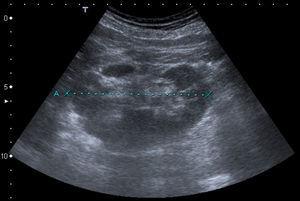

Con los resultados de las pruebas, se decidió realizar un bypass fémoro-femoral cruzado derecho-izquierdo, con el objetivo de garantizar una buena cicatrización de una posterior amputación mayor, necesaria por el grado de isquemia irreversible que presentaba el paciente. Así, en un segundo tiempo, se realizó una amputación supracondílea, siendo finalmente el paciente dado de alta con el muñón en adecuado proceso de cicatrización. Durante el posoperatorio se realizó una ecografía abdominal que informa de la presencia de un riñón ectópico derecho, de localización pélvica, de 10,2 cm de diámetro interpoplar con alguna cicatriz cortical en probable relación con antecedente inflamatorio (figura 2). Se realizó posteriormente una tomografía axial computarizada de abdomen, que confirmó la permeabilidad del bypass fémoro-femoral y la presencia del riñón ectópico irrigado a partir de la arteria ilíaca aneurismática con un calibre de 2,8 cm. Se observó también un aneurisma de aorta abdominal infrarrenal de 4,4 cm (figura 3 y figura 4). El paciente fue considerado candidato a seguimiento en consulta externa sin tratamiento de ambos aneurismas por los siguientes motivos: riñón derecho único, con arteria renal dependiente de arteria ilíaca común aneurismática, ERC estadio 3B y 77 años de edad.

Figura 2. Ecografía renal.